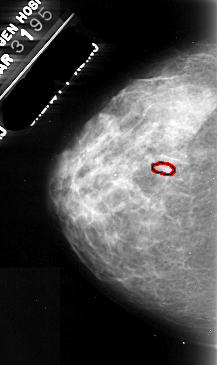

A_1105_1.RIGHT_CC

RIGHT_CC LINES 4381 PIXELS_PER_LINE 2671 BITS_PER_PIXEL 16 RESOLUTION 42 NON_OVERLAY

FILE: A_1105_1.LEFT_MLO.OVERLAY

TOTAL_ABNORMALITIES 1

ABNORMALITY 1

LESION_TYPE CALCIFICATION TYPE PLEOMORPHIC DISTRIBUTION CLUSTERED

ASSESSMENT 4

SUBTLETY 2

PATHOLOGY MALIGNANT

TOTAL_OUTLINES 1

BOUNDARY